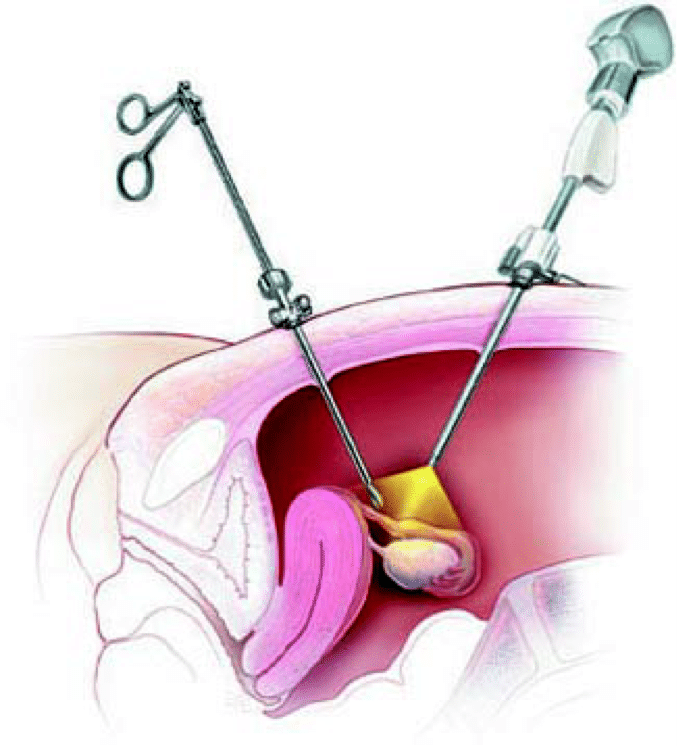

Современные методы лапаротомии и миомэктомии